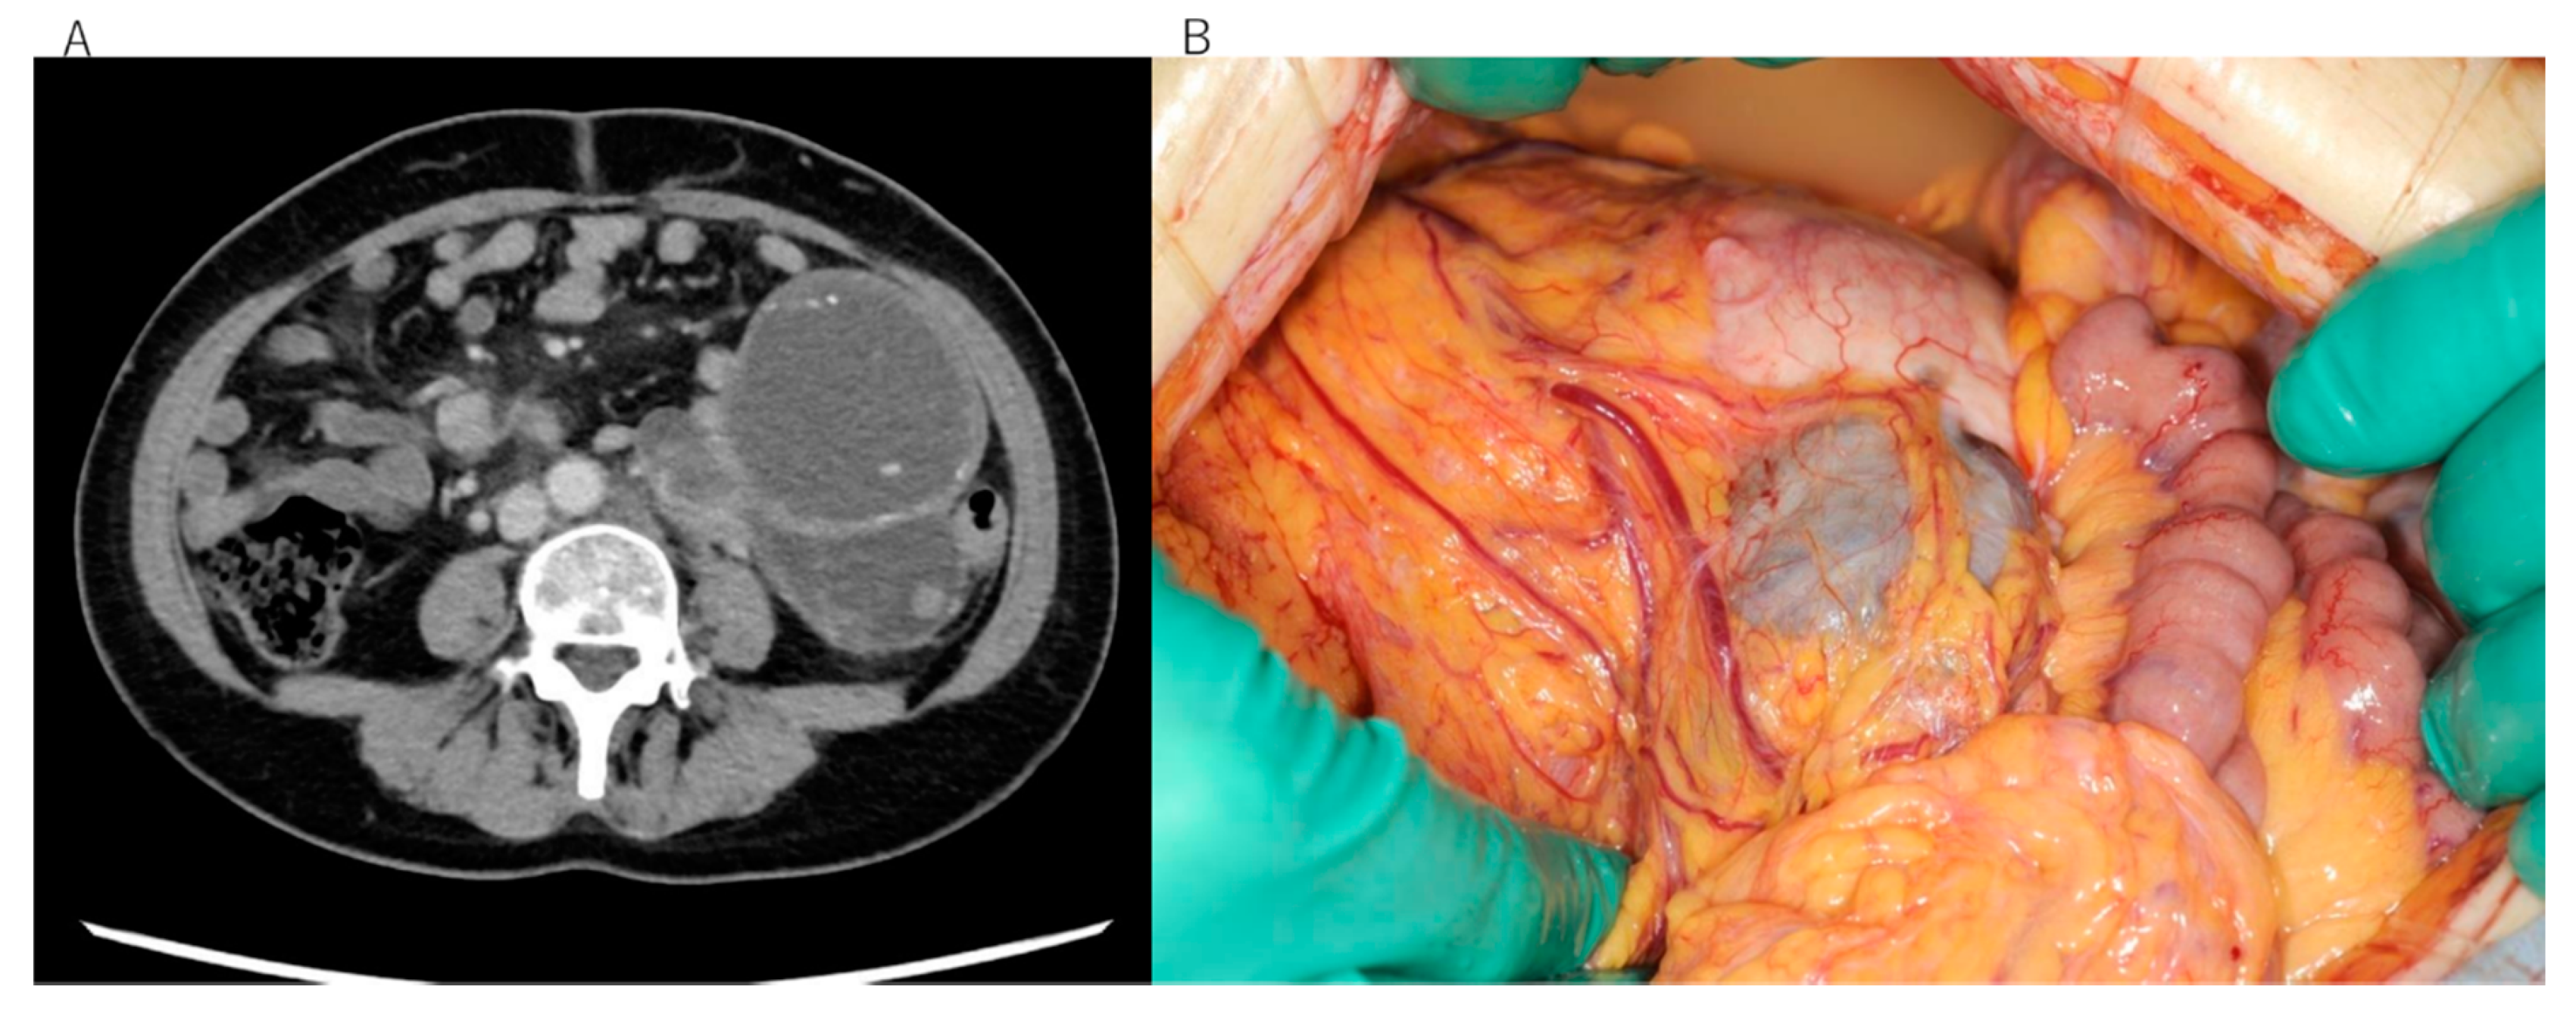

This study included two patients with EIATs, one from Seirei Hamamatsu General Hospital and one from Kobe City Medical Center Hospital. The diagnosis was malignant transformation of extragonadal endometriosis in both cases, according to criteria recommended by a Japanese survey [11]. Histologically, the tumor in patient 1 was identified as clear cell carcinoma arising in the left sigmoid colon (Figure 1A–C), whereas that of patient 2 was identified as undifferentiated carcinoma arising in the rectum (Figure 2A,B). Neither patient received hormone therapy before these cancers were diagnosed (Table 1). The patients’ characteristics are summarized in Table 1. Clinical information was obtained retrospectively from electronic medical records. The study was conducted in accordance with the tenets of the Declaration of Helsinki and Title 45 (United States Code of Federal Regulations), Part 46 (Protection of Human Subjects), effective 13 December 2001.

Figure 2.

Clinical and pathological images of the rare-site endometriosis-associated cancer (RSEAC) in patient 2. (A) Surgically dissected uterus and rectum; yellow arrows indicate the location of the RSEAC. (B) Hematoxylin and eosin staining showing undifferentiated carcinoma.